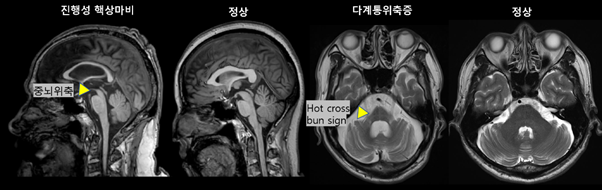

자기공명영상은 파킨슨병 진단보다는, 이차성 파킨슨증 (뇌혈관병변, 수두증, 종양 등)이나 비정형 파킨슨증후군 (진행성 핵상마비, 다계통 위축증 등) 을 감별하는데 큰 가치를 가진다. 예를 들어 비정형 파킨슨증후군 중 진행성 핵상마비는 중뇌 위축(hummingbird/morning-glory sign) 소견이 보이고, 다계통 위축증에서는 자기공명영상 중 교뇌의 ‘hot-cross-bun’ 소견이 보일수 있다 (그림 5). 다만 질환의 유병기간, 중증도에 따라 특이도의 변동이 있어서 단독 확진 근거로는 제한점이 있다.